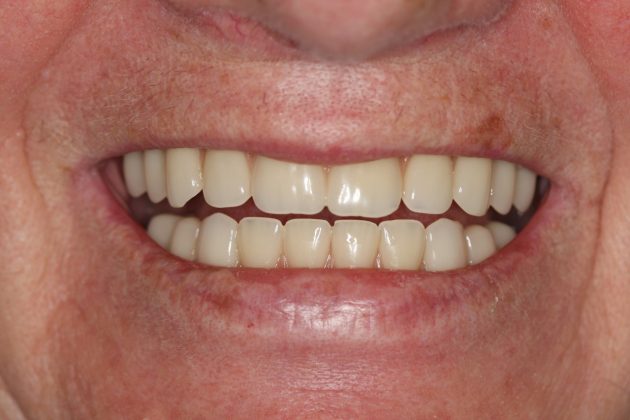

借助MAC精确导板辅助,港星罗家英8分钟长新牙

七旬老人在麦芽口腔实现5颗钉种半口

数字化精确种牙领航,麦芽实现即种即用